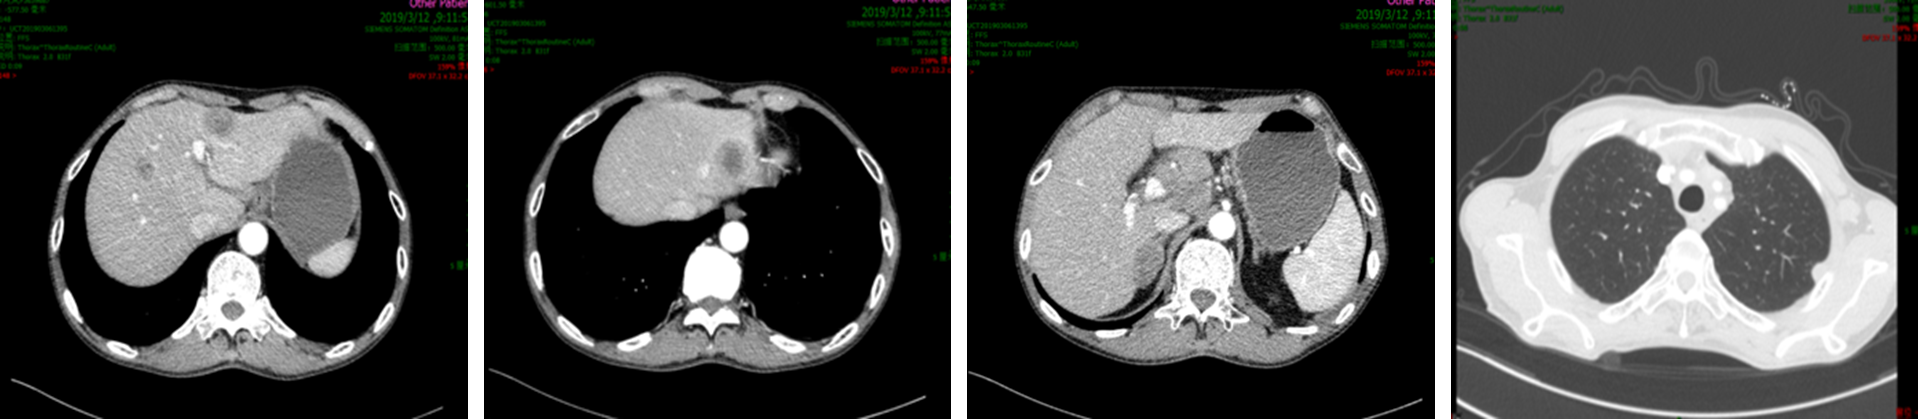

2019年3月胸腹部CT检查发现肝脏、肝门区淋巴结、肺内出现新发转移病灶。患者出现贫血,消瘦,纳差,白天卧床时间大于50%,PS评分3分。

image009.png

图3  一线治疗进展后胸腹部CT